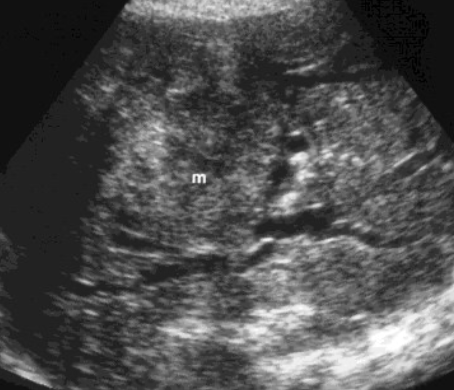

2D US: multiple hypoechoic masses, lobular, poor margins, encases vasculature, periportal enlarged hypoechoic lymph nodes, splenomegaly

color doppler:

DDX: METS, HCC